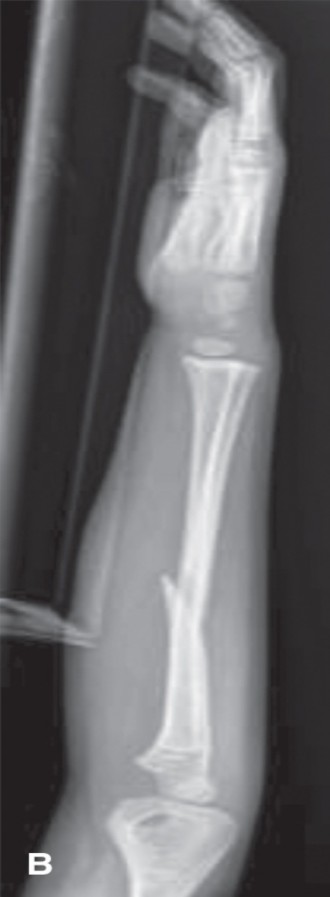

CASE 5 A 4-year-old girl fell from a playground structure, suffering the injury shown in the x-ray (Fig. 10–6A and B).

Figure 10–6 B